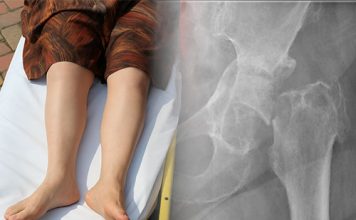

Travma hastasında dolaşımın erken değerlendirilmesi ve hızlı yönetimi, yaşamsal öneme sahiptir. Travmaya bağlı ölümlerin önemli bir kısmı, tedavi edilebilir kan kayıpları nedeniyle meydana gelir....